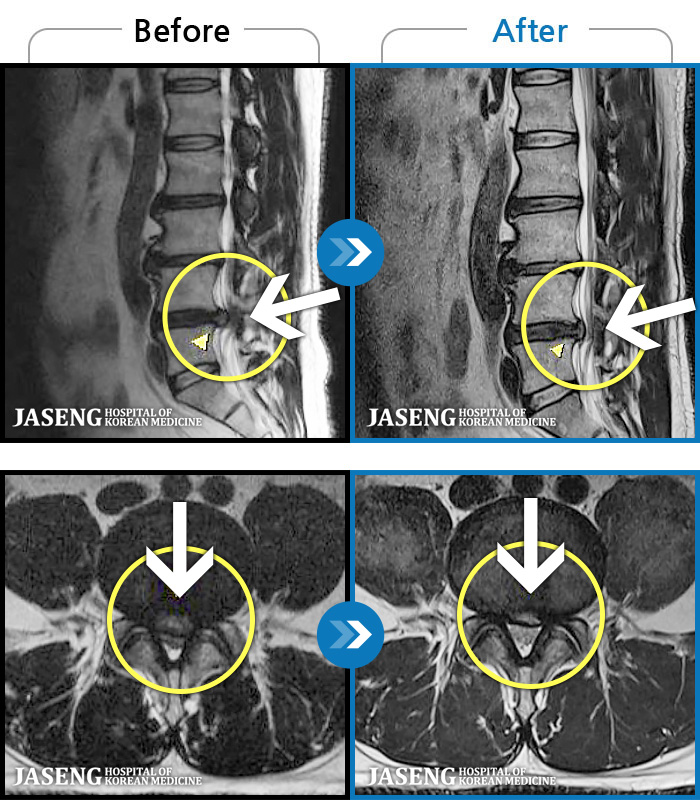

MRI ġ

MRI ũ ʸ Ȯϼ.